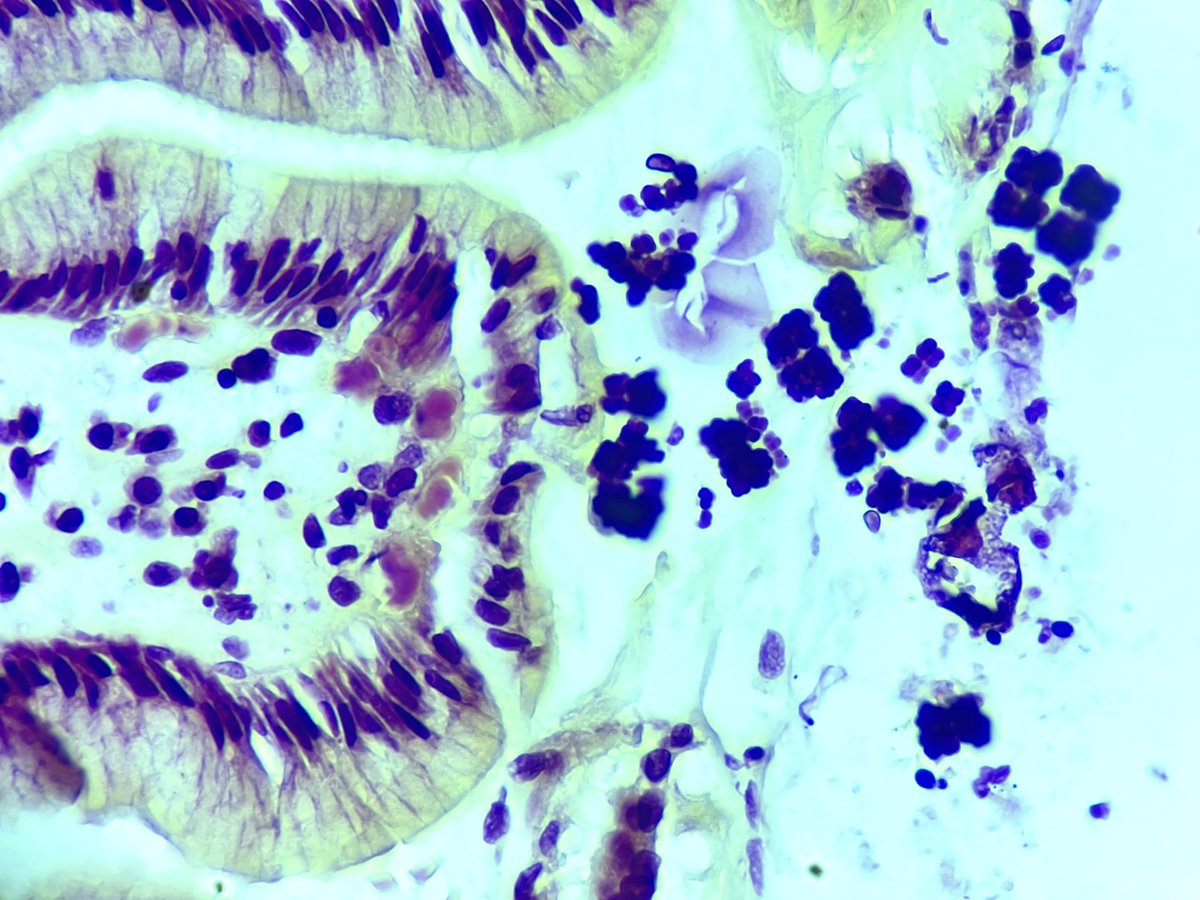

Not my typical #gupath #gynpath post but an interesting one for trainees! Colon biopsy for GI bleed, clinical concern for IBD. #pathboards

Not my typical #gupath #gynpath post but an interesting one for trainees!

Colon biopsy for GI bleed, clinical concern for IBD.

#pathboards